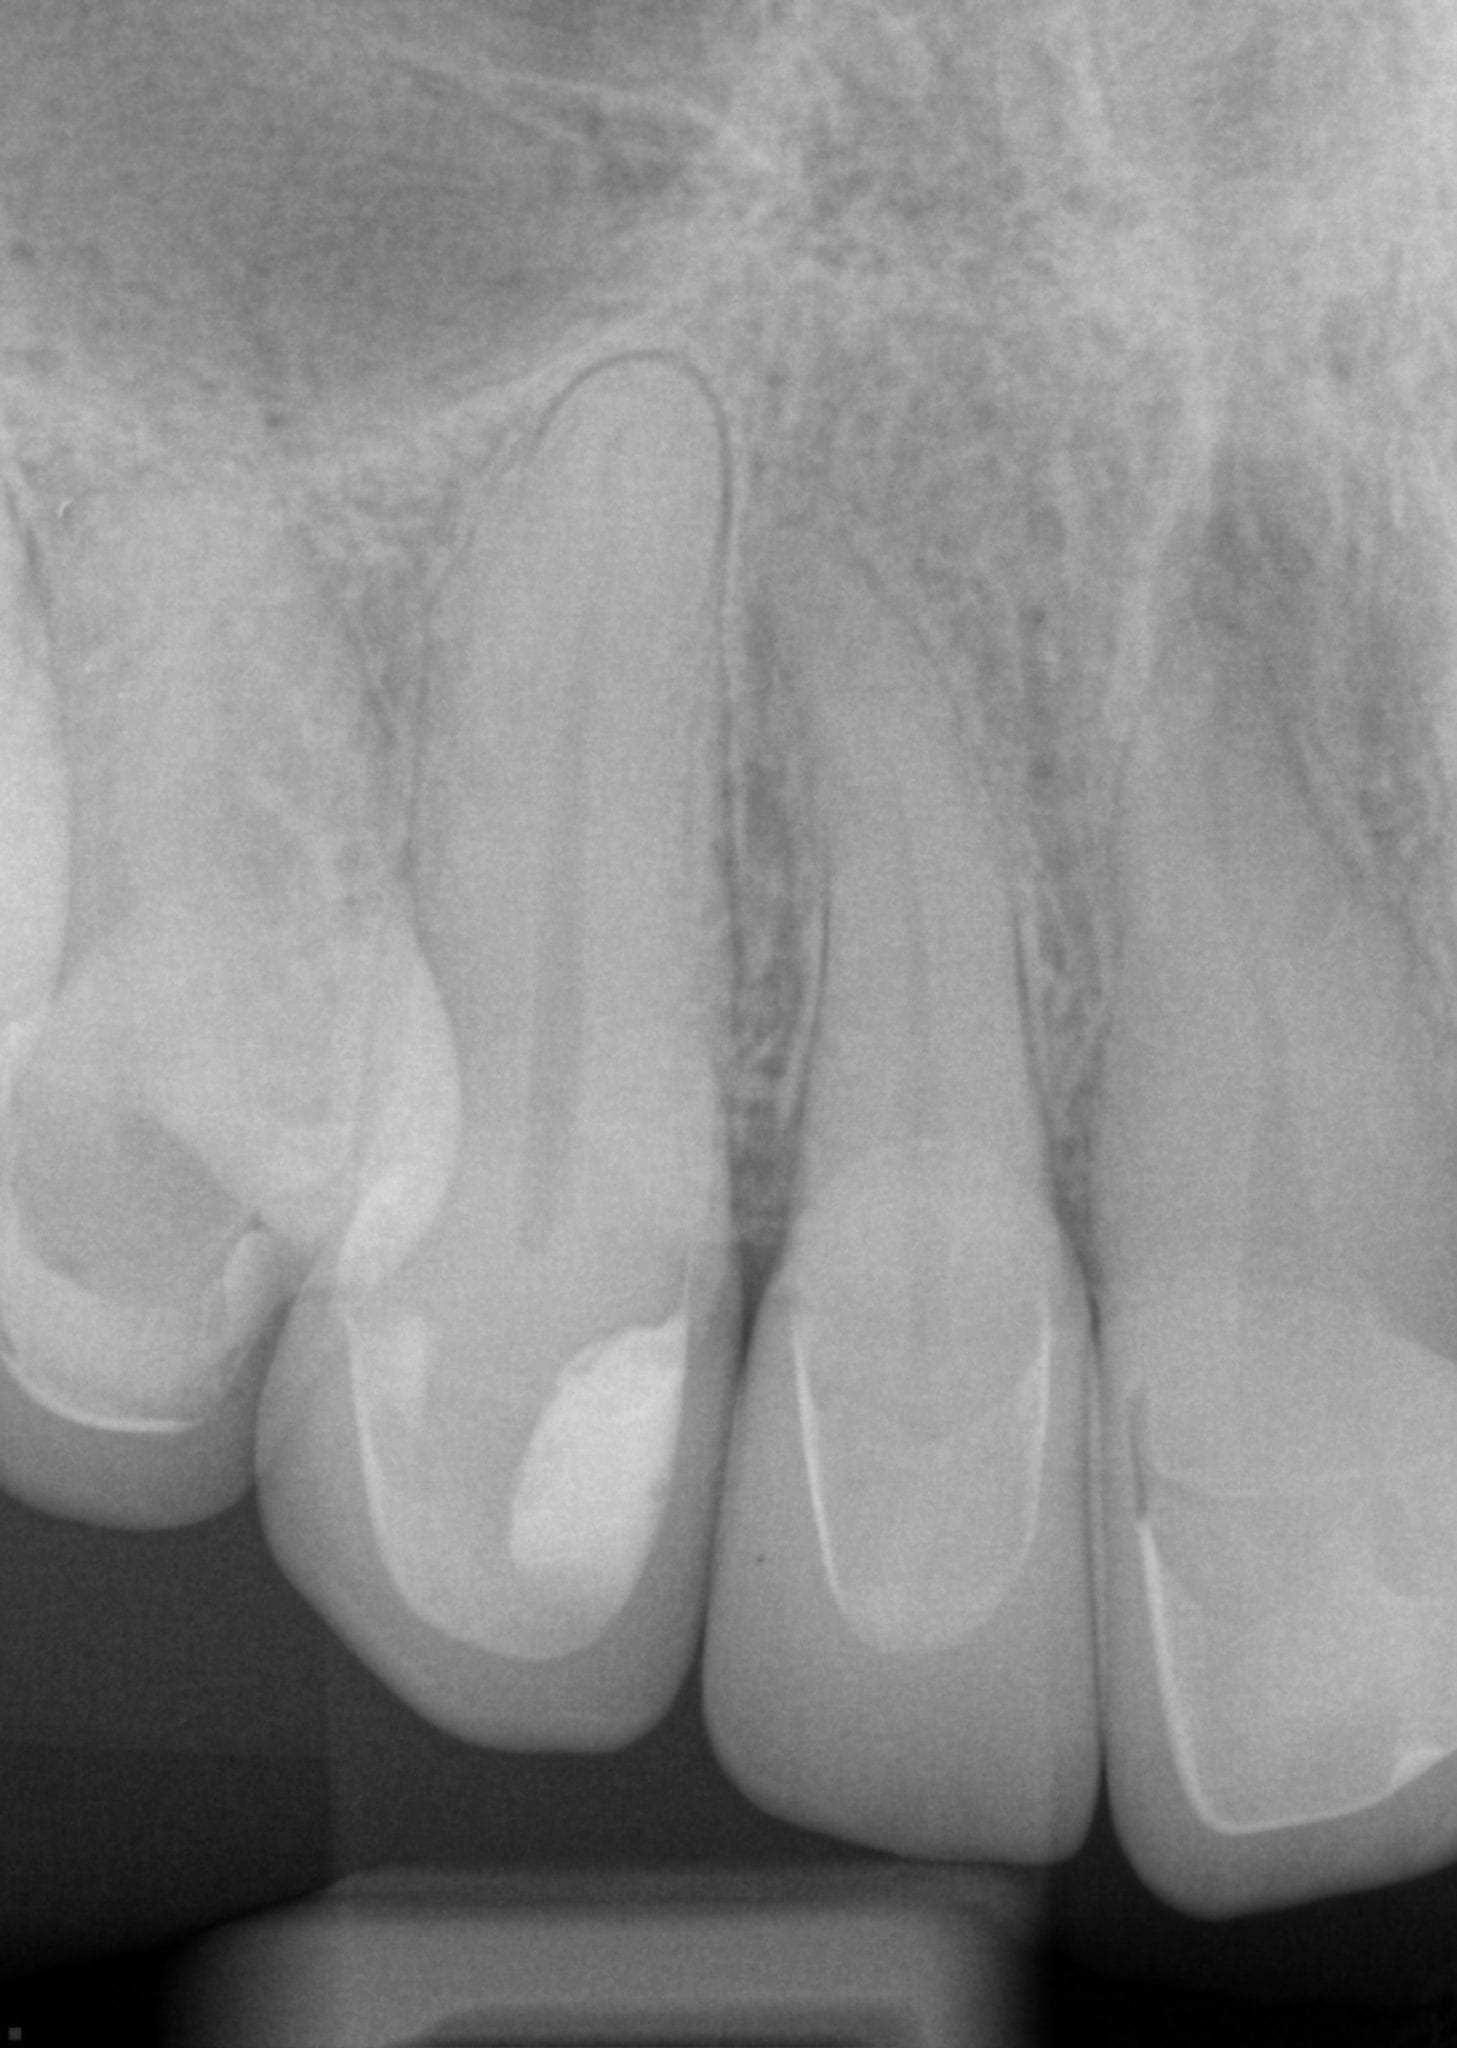

One Month Post Op with Radiographs